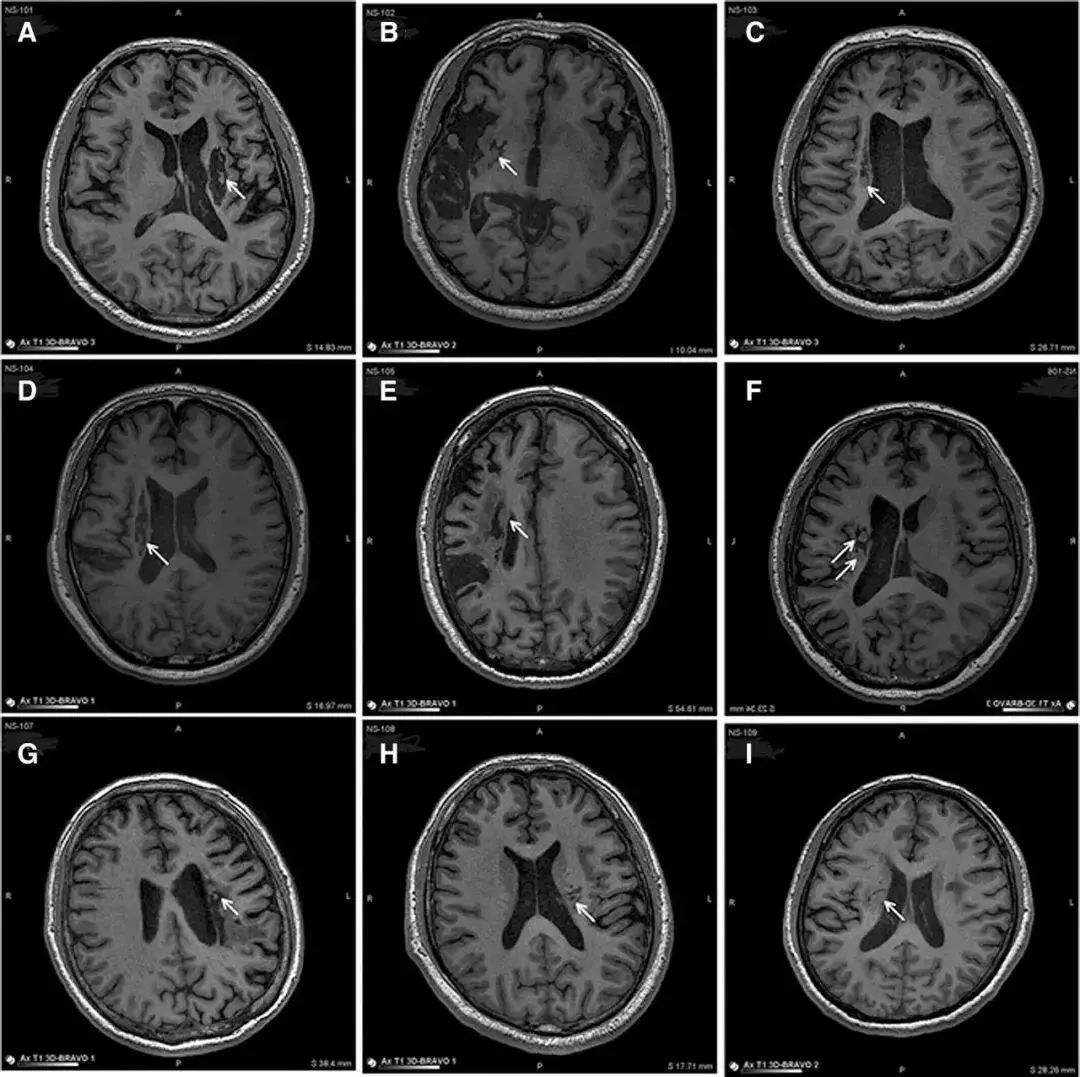

脑中风发生后,免疫反应会被激活,导致炎症反应和免疫细胞的过度激活,进一步加重脑损伤。而间充质干细胞有助于平衡免疫系统,可以帮助抑制这些过度激活的免疫细胞,减轻炎症反应,从而对脑中风患者的康复起到积极作用。 一项研究表明,在9名年龄不等的中风偏瘫患者实验中,应用干细胞移植到脑内梗塞灶取得了一定的临床效益,且连续24个月的随访数据都显示出干细胞的耐受性很好,没有不良并发症,证明了干细胞应用的安全性。 △ 9例患者的影像学显示病变区域的组织都发生了明显变化 他们发现,移植到脑内梗塞病灶的干细胞,通过分化为神经系统的各类细胞、分泌营养因子,促进神经和血管再生,修复受损的血-脑脊液屏障,减轻炎性反应等促进脑梗死动物的神经功能恢复,让9例临床患者偏瘫的症状得到了明显改善。 这也是干细胞发挥免疫调节功能,促进微血管及神经网络修复来干预中风后遗症的关键。 03 干细胞移植治疗脑中风的安全性及有效性评估